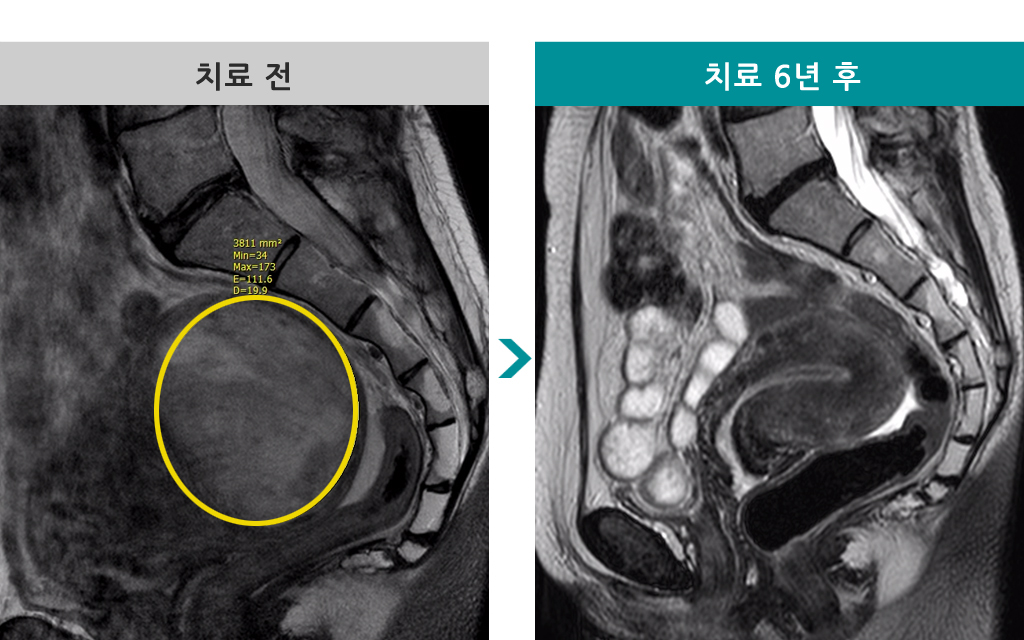

43세 [자궁근종 색전술] 전후 MRI사진 비교 - Before & After

43세 [자궁근종 색전술] 전후 MRI사진 비교

▶ 주치의 : 김재욱 원장

▶ 환자 : 43세 여성

▶ 질환 종류 : 7.2 x 6.5cm 자궁근종

▶ 질환으로 인한 불편증상 : 생리통, 생리과다

▶ 치료 경과 : 2011년 색전술 2회 받고 근종 완전괴사됨. 2017년 추적 MRI 검사에서 거의 흔적이 보이지 않게 감소함.